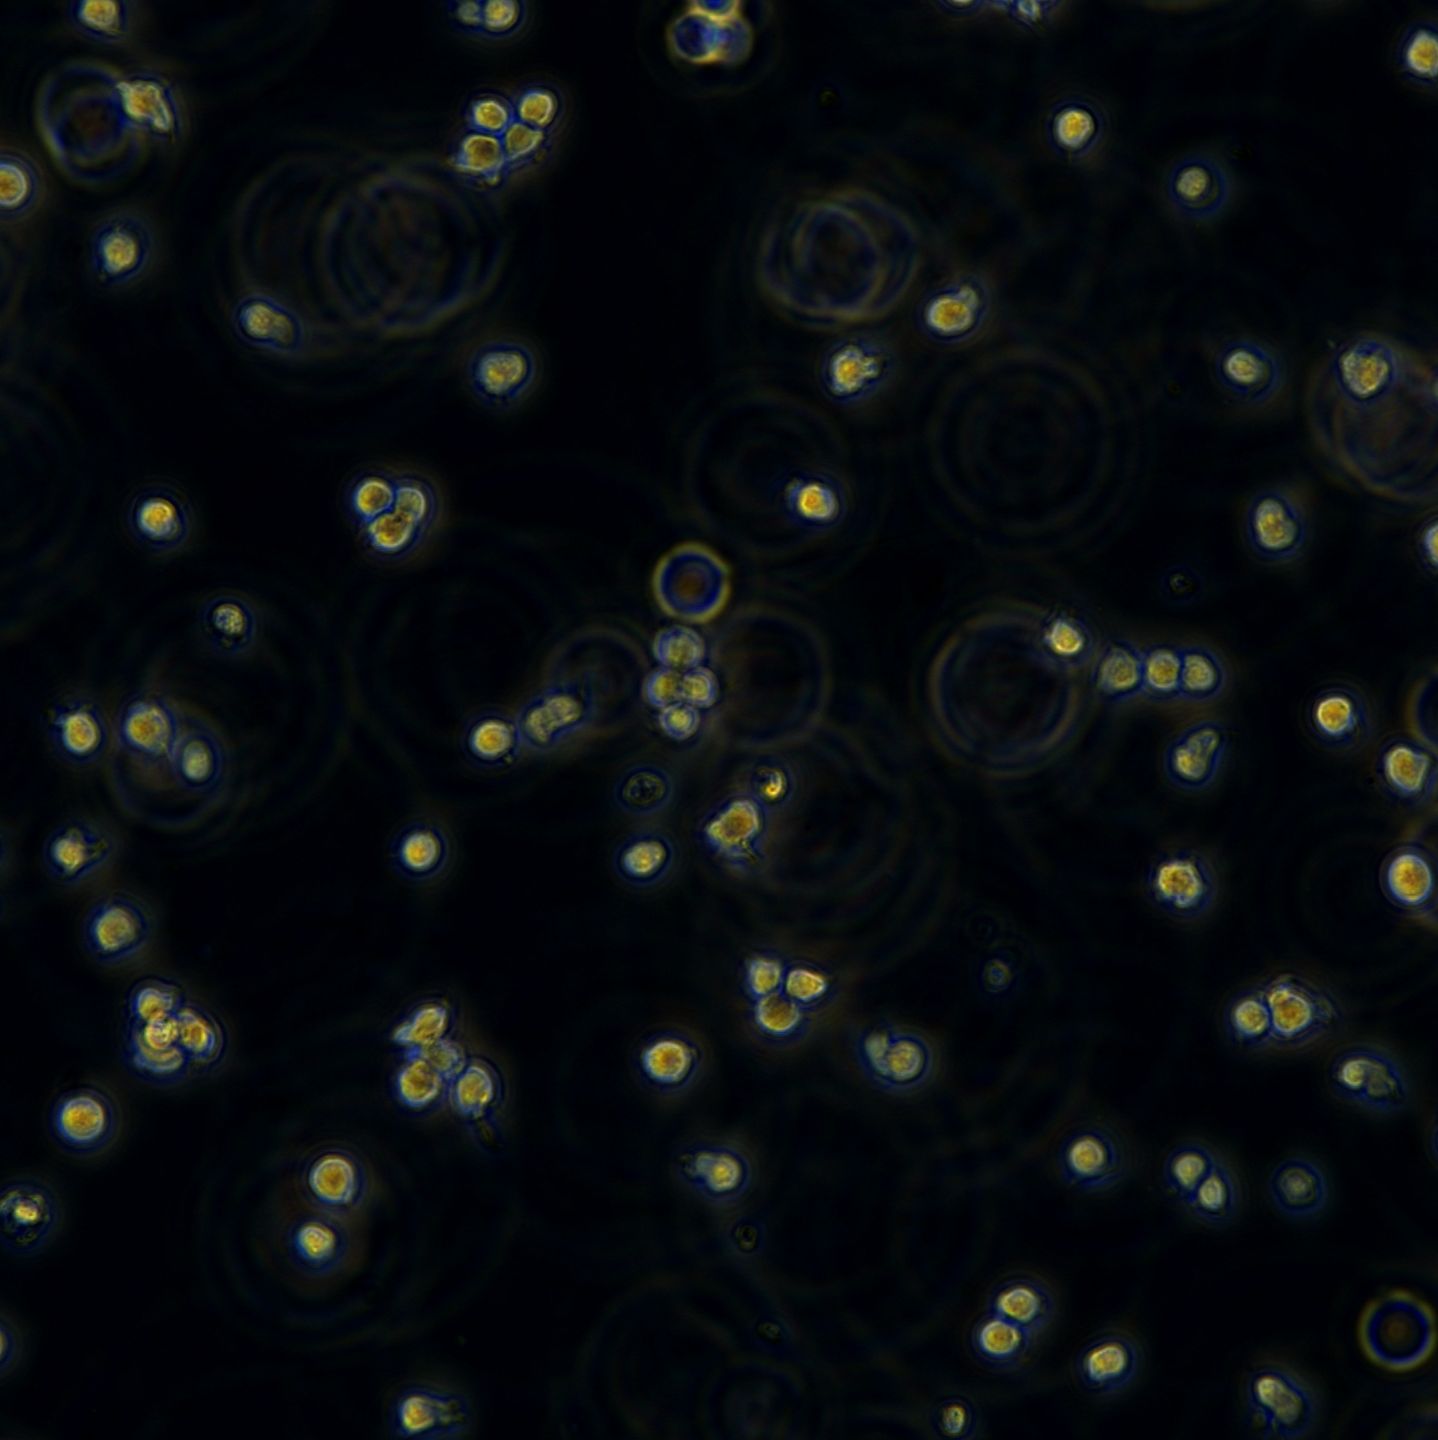

Jurkat细胞(人外周血白血病T细胞),是一种悬浮细胞。我的经验如下:1、培养液:RPMI1640,15%小牛血清,2%Na2CO3,1%HEPES,青霉素100IU/1ml,庆大霉素100IU/ml;2、培养条件:5%CO2,37度,30%湿度;3、细胞复苏:要快速将冻存管放入37度水中,不断轻轻摇晃,直到细胞完全溶解,加入10ml左右的培养液,800~1000rpm,10分钟离心,之后倒掉液体,加入新的培养基就可以进行培养了;4、细胞培养:起初进行传代时由于细胞刚刚复苏,长得比较